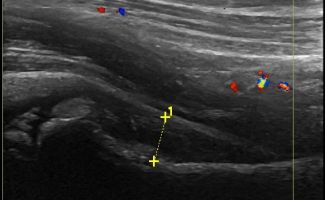

- Θυλακίτιδα: Συλλογή υγρού στο θύλακο του τένοντα του Λαγονοψοΐτη

- Πρόσκρουση του τένοντα του Λαγονοψοΐτη (Snapping Hip)

- Δυναμικές δοκιμασίες: Το υπερηχογράφημα είναι μία δυναμική εξέταση, κάτι που σημαίνει ότι η διαγνωστική πληροφορία μπορεί να προκύψει κατά τη διάρκεια της κίνησης. Αυτή η δυνατότητα του υπερηχογραφήματος είναι ιδιαίτερα σημαντική για την εξέταση του ισχίου, επιτρέποντας την αξιολόγηση της σημειολογίας πρόσκρουσης (snapping hip) που μπορεί να αφορά τον εσωτερικό τένοντα του λαγονοψοΐτη ή την εξωτερική λαγονοκνημιαία ταινία.